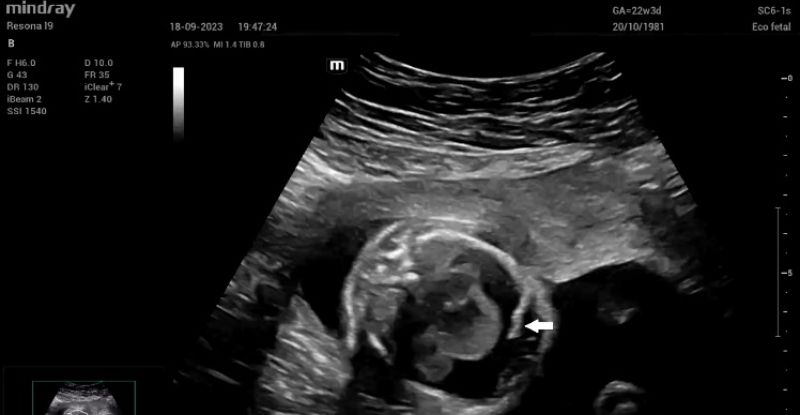

Upon admission, fetal echocardiography revealed a well-defined intrapericardial bilobed mass, measuring 20 mm x 16 mm x 10 mm, located in the free wall of the left atrium and left ventricle at the level of the mitral valve and presenting with severe pericardial effusion (Fig. 1).

Figure 1: Septal four-chamber view of the fetal heart. The teratoma (white arrow) is clearly seen at the level of the mitral valve.